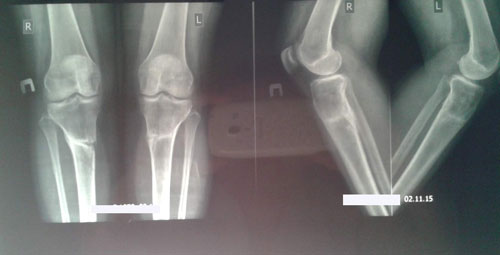

Здравствуйте, Светлана! рентген получили, сращение отличное. Вам всё разрешено без ограничений (спорт, каблуки и т.д.). Кроме: беременеть в течении первых 6 месяцев с момента снятия аппаратов.

Рентген в 1,5 месяца с момента снятия аппаратов.